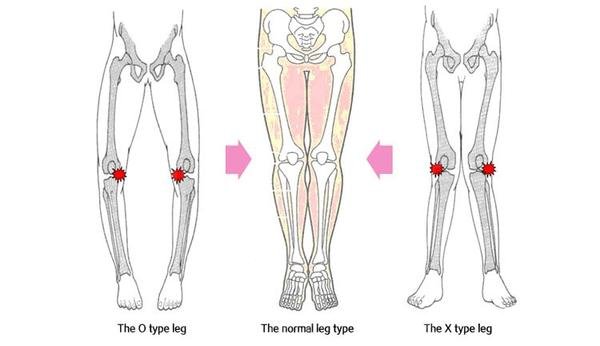

1. Die meeste mense wat knievervangings kry, is weens permanente skade aan die kniegewrig weens artritis. Sowat 45% van alle mense ouer as 60 jaar ontwikkel osteo-artrtis, en van hierdie mense kry erge slytasie van kraakbeen in die knie kry. As mens oorgewig is, ontwikkel tot 66% van mense artritis, en meestal knie-artritis. As die kraakbeen in die knie só verweer het dat been om been skuur met elke tree, kan dit baie pynlik raak en is ‘n knievervanging al uitweg.

3. In sommige gevalle, waar net die binnekant of die buitekant van die kniegewrig verweer het, kan ‘n halwe knievervanging gedoen word. Met ‘n halwe knievervanging voel die knie ná die operasie steeds soos jou eie knie, omdat glad nie deur tendons, ligamente of spiere gesny word nie. Die knieligamente moet gesond wees om ‘n halwe knievervanging te kan doen.

4. Met ‘n volle knievervanging word wel deur die kruisligamente gesny.